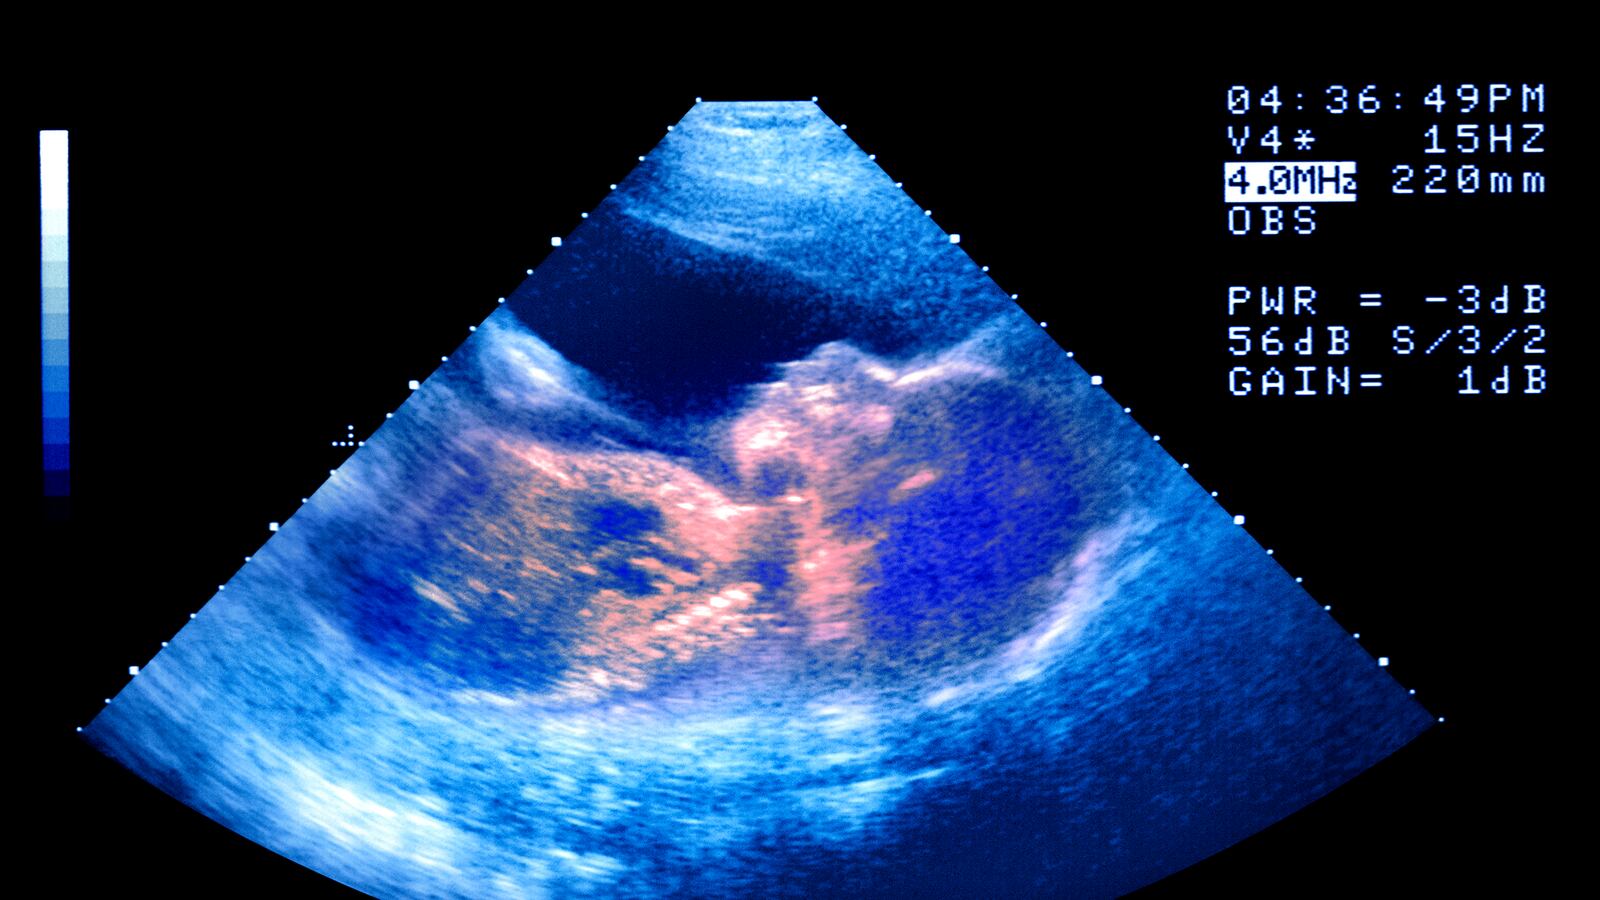

The vast majority of infertile African women can’t get pregnant because of fallopian tubes clogged by infections. That makes them, in one sense, perfect candidates for in vitro fertilization because IVF works best on women who have clogged tubes and no other hormonal issues. Doctors bypass the tubes and place the embryo right in the womb. Skeptics point out that money should be used to prevent infections in the first place.